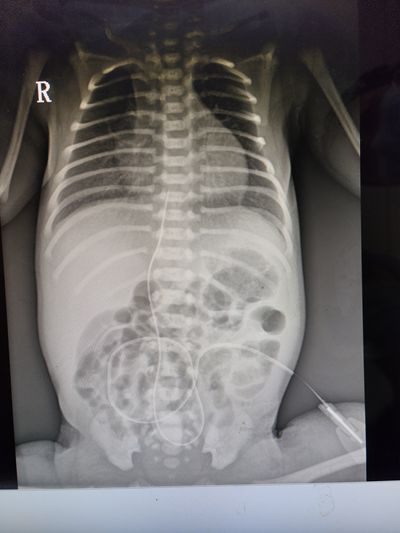

在征得患兒家長(zhǎng)同意及充分的術(shù)前準(zhǔn)備后,治療團(tuán)隊(duì)嚴(yán)格按照臍靜脈置管術(shù)操作流程,精準(zhǔn)實(shí)施每個(gè)步驟的操作。經(jīng)床旁攝片顯示導(dǎo)管末端位置準(zhǔn)確,置管非常成功。術(shù)后,經(jīng)過(guò)保暖、吸氧及經(jīng)臍靜脈導(dǎo)管輸注營(yíng)養(yǎng)液和血管活性藥物等救治措施后,患兒病情得到明顯改善,目前正在進(jìn)一步康復(fù)中。